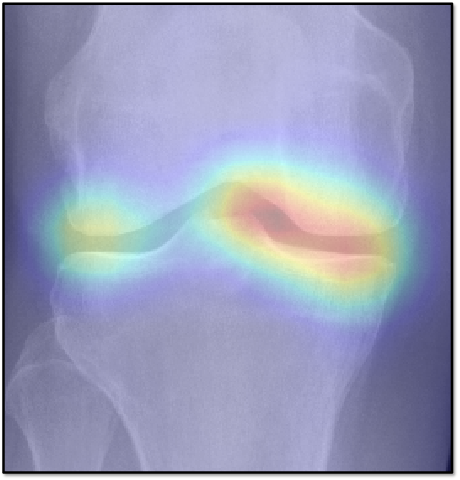

While machine learning-based approaches yield stronger prediction than conventional statistical models, (e.g. LR), they are less transparent, which can lead to lack of trust from clinicians. To address this drawback, various methods have been developed to explain the decisions of ”black-box systems” [24, 26, 27]. As such, we utilized the GradCAM approach [24] that allowed us generating an attention map, in order to highlight the zones where the CNN has paid its attention. While being attractive, this approach can also lead to wrong interpretations, i.e. there is no theoretical guarantee that the neural network identifies causal relationships between image features and the output variable. Therefore, a thorough analysis of the attention maps is required to assess the significance of certain features and anatomical zones picked-up by the model. Such analysis, however, could enable new possibilities for investigation of the visual features. For example, we observed interesting associations in the GradCAM-generated attention maps (Figure 5), some of which are not captured by KL grading. As such, tibial spines (previously associated with OA progression [28]) were highlighted in multiple attention maps. These associations, however, do not hold for all the progressors.

Refer to caption

(a) KL-2 to KL-3, slow

(b) KL-2 to KL-3, fast

(c) KL-3 to KL-4, slow

(d) KL-3 to TKR

(e) KL-2 to KL-3, fast

(f) KL-3 to KL-4, fast

Figure 4: Examples of GradCAM-based attention maps for the knees having osteoarthritis at baseline and progressed in the future. Fine-grained sub-types of progression are also specified. The presented images are of 140×140140140140\times 140 mm.